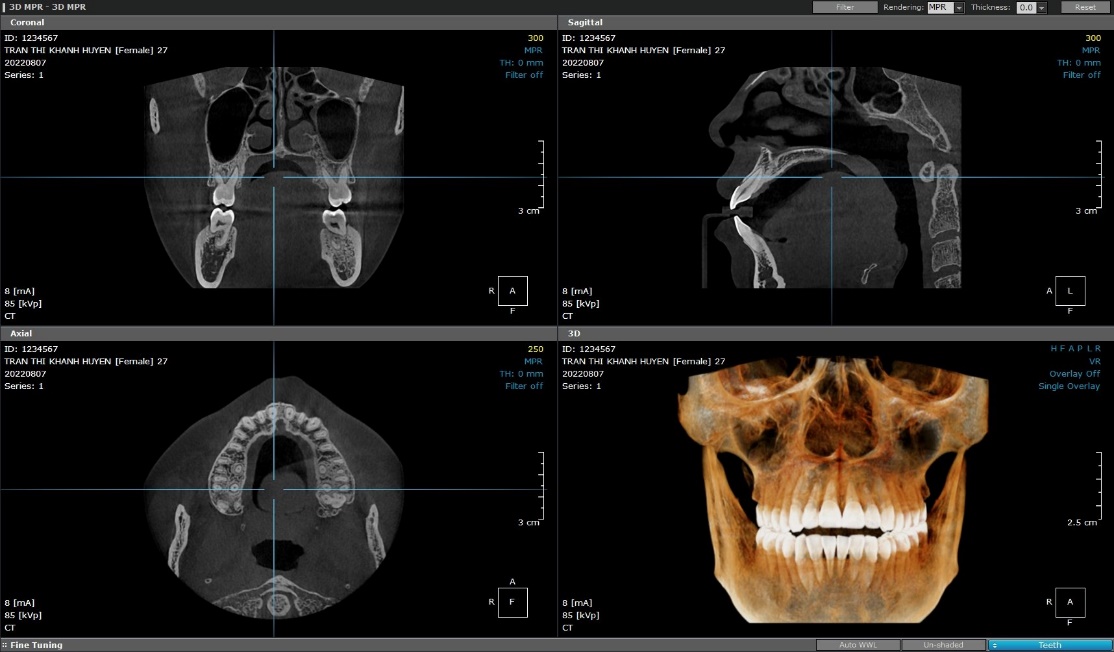

Khoa Chẩn đoán hình ảnh là khoa cận lâm sàng, thực hiện các kỹ thuật tạo ảnh y học để chẩn đoán bệnh và theo dõi kết quả điều trị, bằng các thiết bị x-quang, siêu âm, chụp cộng hưởng từ MRI, cắt lớp vi tính,…

- Chụp cắt lớp vi tính (CLVT): chụp CLVT hàm mặt, chụp CLVT xoang, chụp CLVT vùng răng bất kỳ, chụp panorama (răng toàn cảnh), chụp khớp thái dương hàm, chụp Cephalo mặt nghiêng – mặt thẳng, chụp cườm tay, chụp sọ ngửa.